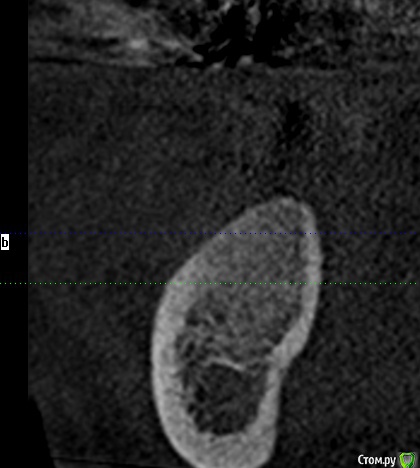

Тимур86 Опубликовано 5 ноября, 2019 Автор Поделиться Опубликовано 5 ноября, 2019 Не стоит бороться со своими желаниями... я бы удалил и гисту провёл, а потом можно и астру думаешь оно инкапсулированное? Мне кажется это типа остеомы, хотел забрать трепаном перед подготовкой ложа и на гистологию Ссылка на комментарий

red_butler Опубликовано 5 ноября, 2019 Поделиться Опубликовано 5 ноября, 2019 думаешь оно инкапсулированное? Мне кажется это типа остеомы, хотел забрать трепаном перед подготовкой ложа и на гистологиюДа, вроде капсула есть 1 Ссылка на комментарий

Тимур86 Опубликовано 5 ноября, 2019 Автор Поделиться Опубликовано 5 ноября, 2019 Ну вот на панораме вроде есть, а на срезах не сказать Ссылка на комментарий

Bier Опубликовано 5 ноября, 2019 Поделиться Опубликовано 5 ноября, 2019 а анамнез какой? может это биоосс в кисте? Ссылка на комментарий

Тимур86 Опубликовано 1 октября, 2020 Автор Поделиться Опубликовано 1 октября, 2020 Есть похожая ситуация! Но тут сложнее :глубже, и в непосредственной близости с нервом... У кого какие мысли? Ссылка на комментарий